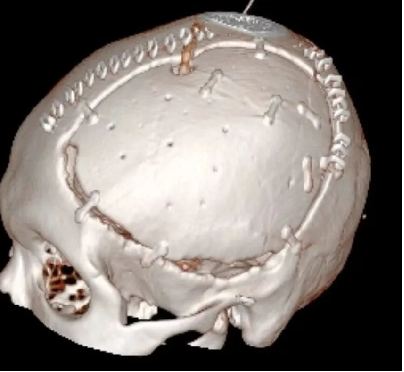

大骨瓣減壓技術常用在重症顱腦損(sǔn)傷的救治,術後常遺留有顱骨缺損。傳統(tǒng)的顱骨修(xiū)複材料雖取材方便,但存在明顯的排斥反應,而自(zì)體顱骨修補恰恰規(guī)避了這一缺點,成了(le)顱骨修複的“金標(biāo)準”。自體顱骨不存在常見的排斥反應,外形匹配、美(měi)觀,真正做到完美“顱”初。

患者術後滿三個月(yuè)再次返院進(jìn)行顱骨缺損(sǔn)修補術,經過完善術前檢查、全(quán)科討論、做好充分手術(shù)準備後,武(wǔ)寧縣總醫院人民醫院院區神(shén)經外科團隊成功為患者完成(chéng)自體顱骨修補術(shù)。